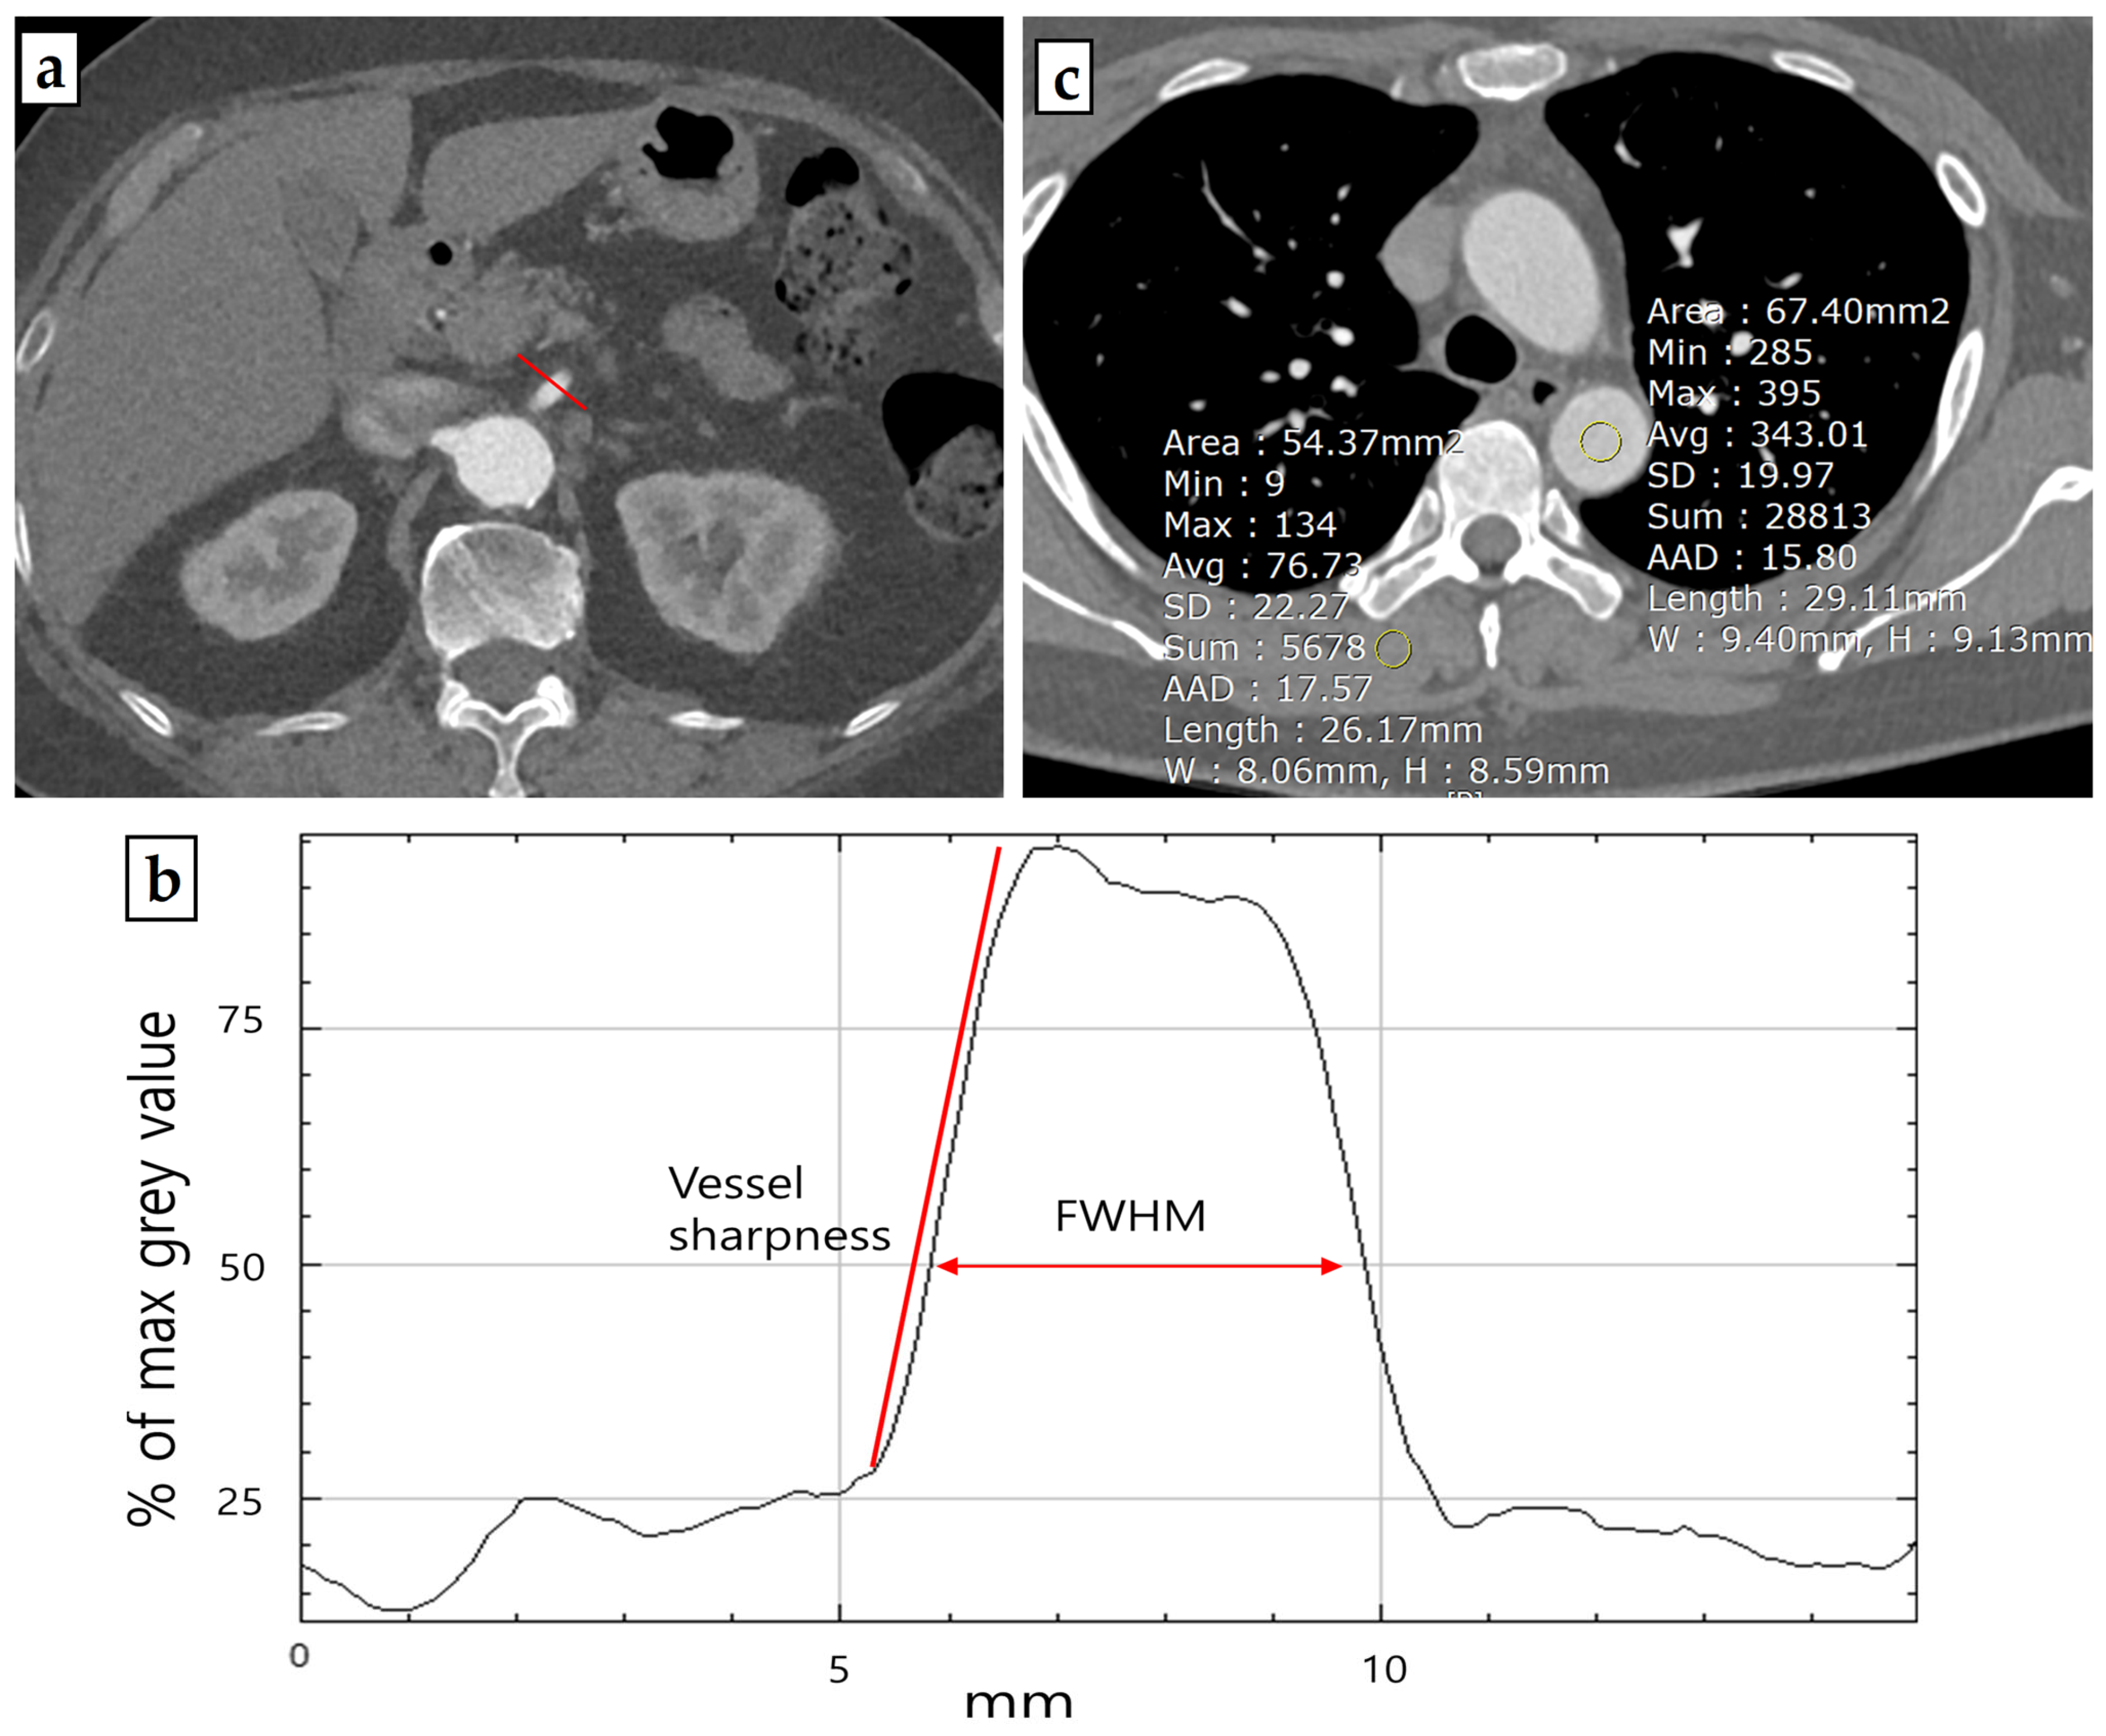

For the estimation of vessel sharpness (VS) [14], a line profile perpendicular to the proximal SMA within 2 cm from the SMA os was generated using FIJI’s [15] “Line Profile” function (Figure 1). The slope of the regression line for the anterior vessel border (sloperise) and the posterior vessel border (slopefall) was calculated with Excel’s built-in “slope function”. The mean of the sloperise and the absolute value of the slopefall were calculated to report quantitative numbers for VS. The proximal SMA was chosen for its good delineation due to the surrounding mesenteric fat, making it suitable for evaluating vessel sharpness. All patients were measured with a window width of 400 HU and a window level of 60 HU in the arterial phase.

Figure 1.

Representative example of a thoraco-abdominal aorta computed tomography angiography (a) (in this case arterial phase scan) used for quantitative image quality analysis. Based on a line profile perpendicular (red line) to the proximal SMA, vessel sharpness and FWHM values were derived (b). Representative example of ROI placement on source images for signal-to-noise ratio (SNR) and contrast-to-noise ratio (CNR) measurements (c).

The Full-Width at Half Maximum (FWHM) edge criterion is a quantitative metric that provides a reliable and robust estimation of a vessel lumen’s edge by defining the boundary at a 50% intensity level between the maximum (lumen) and minimum (tissue). This criterion allows for accurate detection of the vessel lumen and derivation of vessel parameters such as diameter or cross-sectional area [16,17]. To generate FWHM values, the line profile from the proximal SMA computed with FIJI’s “Line Profile” function was used. The length (in millimeters) at the half maximum of the line profile curve was measured to reveal the FWHM value.